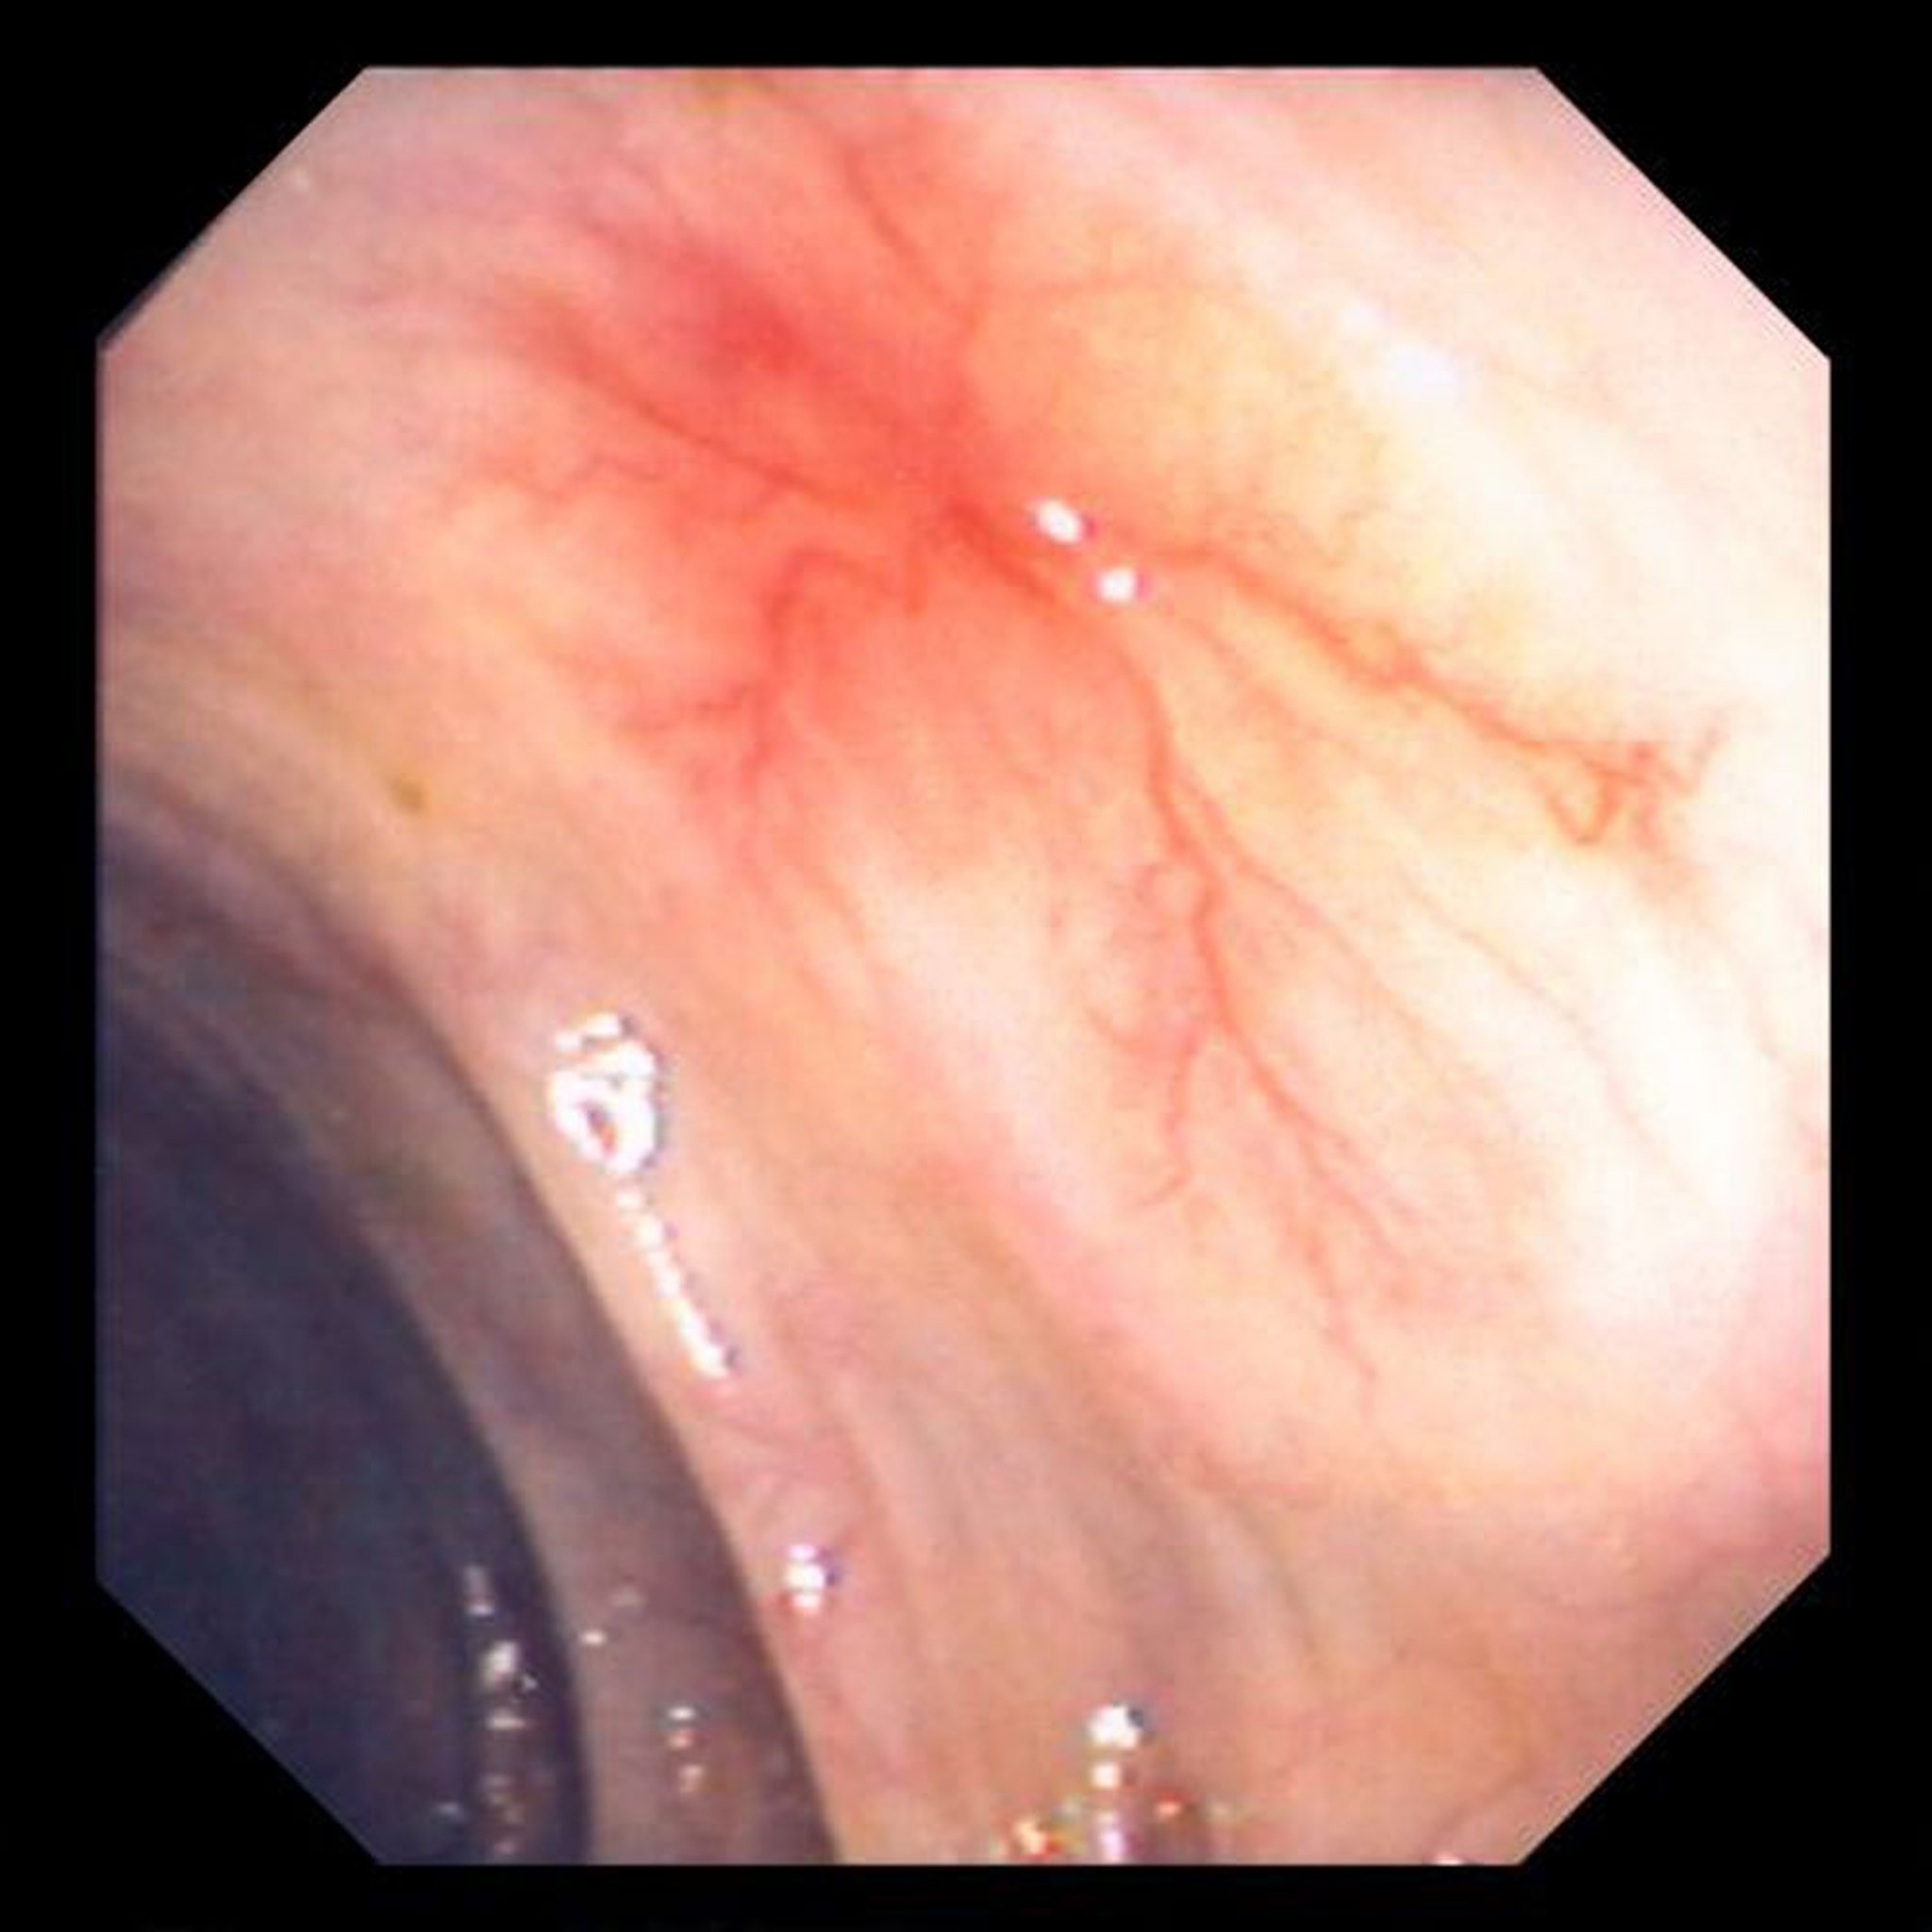

Vasos sanguíneos anormais (angiodisplasia) no intestino

Esta fotografia mostra um vaso sanguíneo anormal na parede do intestino.

Imagem fornecida pelo Dr. David M. Martin.